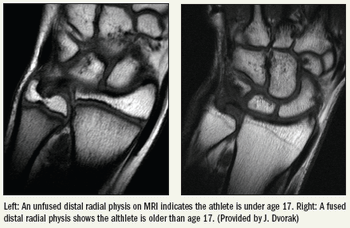

MRI has been adopted as a definitive measure for fair play by the International Federation of Association Football, the governing body for international soccer competition.